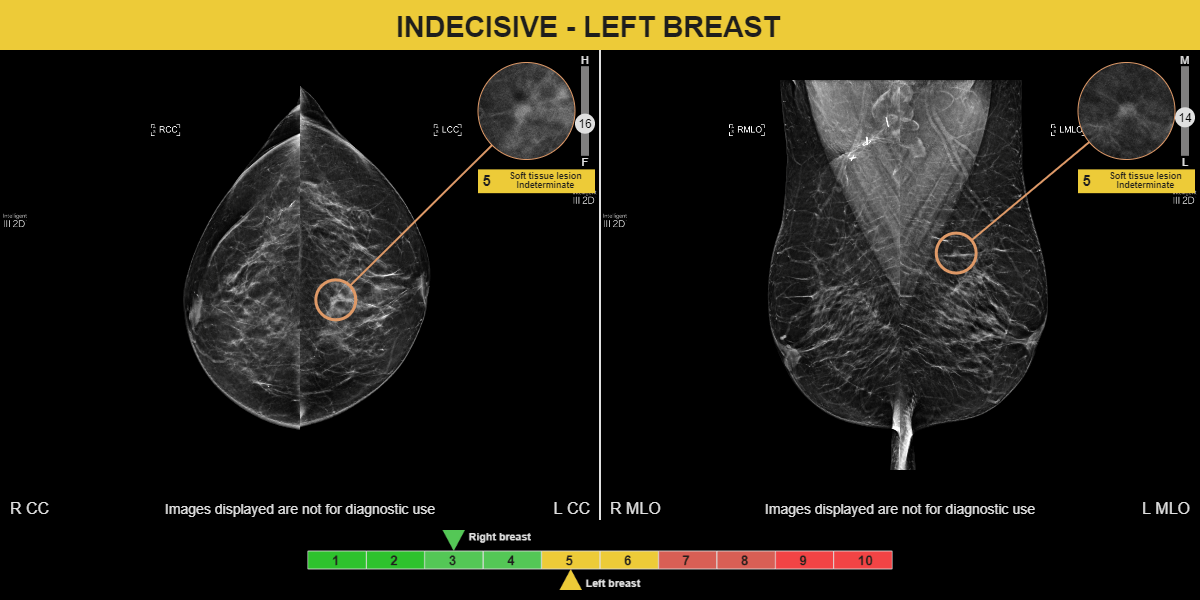

This patient was assessed in 2023. A 5 mm malignant mass was detected on the left breast by the radiologist and MammoScreen, with a score of 6, on the oblique only.

By analyzing the previous 2022 review with MammoScreen, the mass, still smaller and less spiced, is detected by the software with a score of 5 on both incidences.

With this clinical case, MammoScreen was able to successfully detect cancer a year earlier.

This case illustrates well the human limits in terms of detection of small, subtle lesions, the radiologist may, in particular circumstances (fatigue, delay, lack of concentration), overlook this type of lesion.

AI is fundamental in these moments of decreased acuity of the radiologist in order not to ignore these subtle lesions potentially malignant.